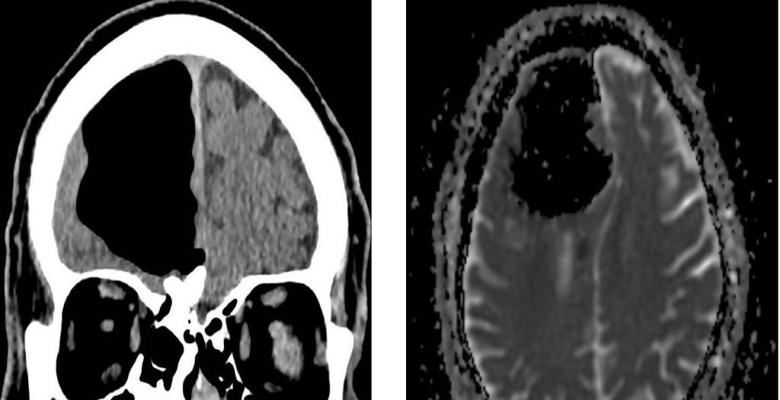

Észak-Írország orvosai meglepődtek, amikor megvizsgálták őket nemrégiben egy 84 éves beteg, aki rossz közérzettel jött hozzájuk. Miután elvégezték az ember fejének mágneses rezonancia leképezését, az orvosok váratlanul rájött, hogy hiányzik a jobb frontális része az agy lebenye. Ehelyett a nyugdíjas koponya levegő volt zsebében. Aztán az orvosok megállapították, hogy a tényleges agyrészlet a beteg sehol sem tűnt el, hanem keverte ezt a kóros irányt az üreg.